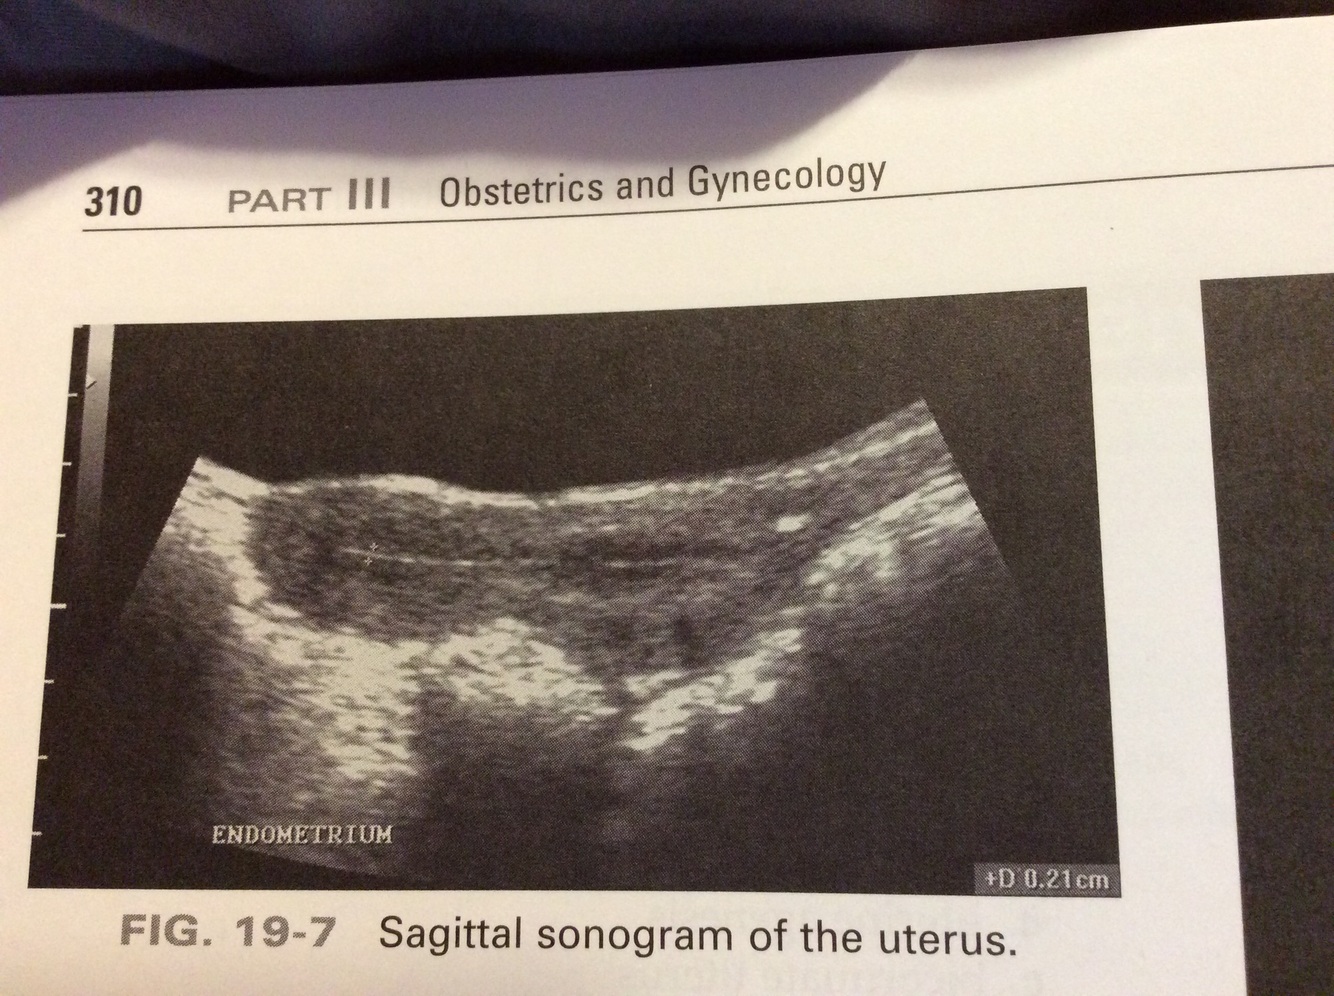

Which of the following correctly measures endometrial thickness?

a) anterior-posterior dimension in the coronal plane

b) transverse dimension in the coronal plane

c) anterior-posterior dimension in the sagittal plane

d) anterior-posterior diameter in the transverse plane

c) The anterior-posterior dimension of the endometrium is only measured in the sagittal plane.

When measuring endometrial thickness, calipers are placed from:

a) superior interface to inferior interface

b) echogenic interface to echogenic interface

c) echogenic interface to hypoechoic interface

d) hypoechoic interface to hypoechoic interface

b: Only the functional layer (echogenic) is included when measuring endometrial thickness. The hypoechoic basal layer or fluid within the endometrium cavity is not included when measuring the thickness of the endometrium.

This sagittal image of the uterus most likely represents a :

a) septae uterus

b) bicornuate uterus

c) premenarche uterus

d) postmenopausal uterus

d: The cervix and corpus appear equal in size (1:1). This is most consistent with a postmenopausal uterus. The cervix is twice the size of the corpus in a premenarche patient (2:1).